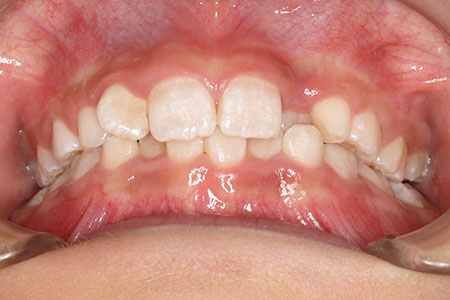

『前歯ががたついて生えてきた』 一般歯科から紹介の患者さんです。 上下4前歯に叢生がみられます。かみ合わせが深く、過蓋咬合。 上顎前歯は舌側傾斜。 永久歯の萌出スペースが上下とも5mmほど足りませんし、 おそらく、これから生えてくる犬歯は八重歯になる状況です。 治療方針としては、小児矯正で叢生(がたつき)を減らし、 永久歯列が生えてから、中学生ごろから本格矯正(マルチブラケット装置)を行います。 十分に側方拡大でスペースを確保し、更に、まだ生えていない永久歯の位置と方向が良ければ、きれいに生えそろうことにより、本格矯正での治療が必要ない場合もありますが頻度的には少ないです。 ある程度はきれいに生えてきても、左右の歯の高さの違いや、歯の回転、角度のズレが残る場合が多いからです。 その多少のがたつきが気にならないのでしたら、小児矯正で終了です。